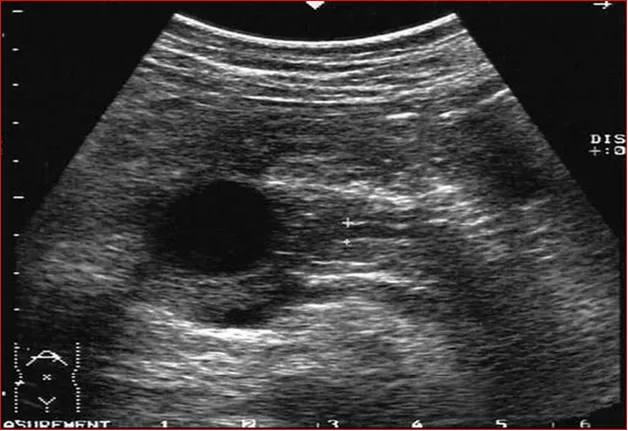

声像图显示:胰头部见无回声,边界清,后壁回声增强。